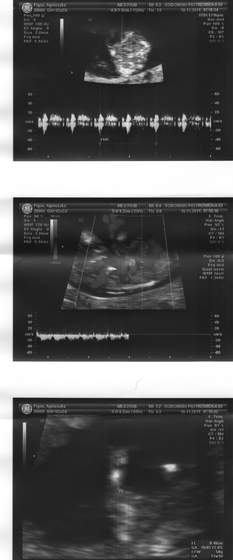

super zdjecia Agagu,az zazdroszcze takich dokladnych!!!nie to co moje rozmazane!super fotki

i gratuluje coreczki!!